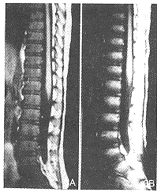

急性白血病组: T1WI: (1)治疗前组38例:腰骶椎38例所有椎体均表现为均匀的信号降低,比相邻的椎间盘和脊髓的信号均明显降低;髂骨38例均表现为低信号,其中3例于髋臼旁见斑片状高信号残留;股骨近段信号降低38例,其中8例股骨头、股骨大转子见斑片状高信号残留,且此8例均有骨骺板存在。 (2)化疗缓解组25例:所有椎体、髂骨、股骨头、股骨大转子及骨干均表现为不同程度的信号增高,达完全缓解者(21例)比部分缓解者(4例)更接近相应的正常骨髓信号(图3、4)。其中9例还作了治疗后追踪观察,第1次为化疗1疗程结束5天内并经临床及骨髓穿刺认为完全缓解时行MRI检查,第2次为2~4周内经骨髓穿刺后行MRI检查。6例2次经骨髓穿刺检查均为完全缓解,但第2次MRI检查椎体信号比第1次略为增高(图5)。复发的3例中,2例再次缓解,经MRI检查,其骨髓信号重新升高。

图3 男,11岁。急性白血病。T1WI示:A.治疗前椎体呈均匀低信号,椎体形态正常;B.治疗后完全缓解其椎体信号明显升高 图4 同图3病例。T1WI示:A.治疗前髂骨、股骨上段信号明显降低;B.治疗后完全缓解其信号升高 图5 17岁。急性白血病。T1WI示:A.治疗前椎体均匀低信号;B.治疗后缓解2天,椎体信号稍升高;C.治疗后缓解3周,椎体信号明显升高